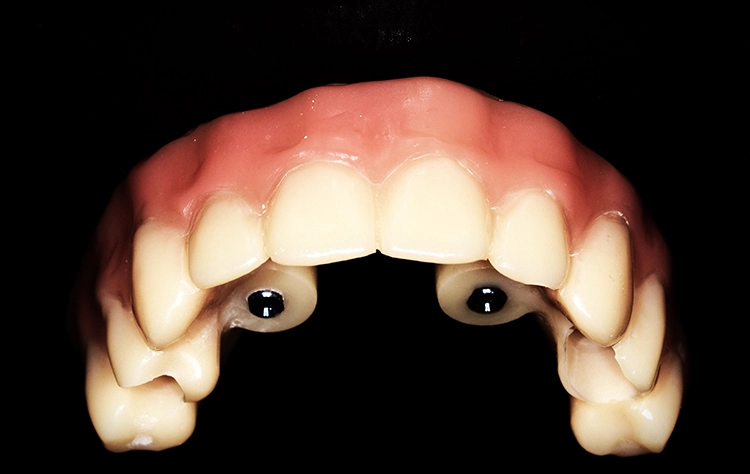

Diese wurden auf die multi-units eingebracht und mit dem Provisorium kunststoffseitig verbunden (Abbildung 7). Die definitive Ausarbeitung erfolgte final im Labor, um eine ideale und hygienisch günstige Struktur zu gewährleisten.

Der Patient wurde am gleichen Tag mit dem festsitzenden Brückenprovisorium entlassen und ausführlich über die Mundhygiene des Langzeitprovisoriums postoperativ aufgeklärt. Abbildung 8 zeigt eine regelrechte Implantatposition in der postoperativen Panoramaschichtaufnahme. In Abbildung 9 ist die postoperative Versorgung in situ zu sehen.